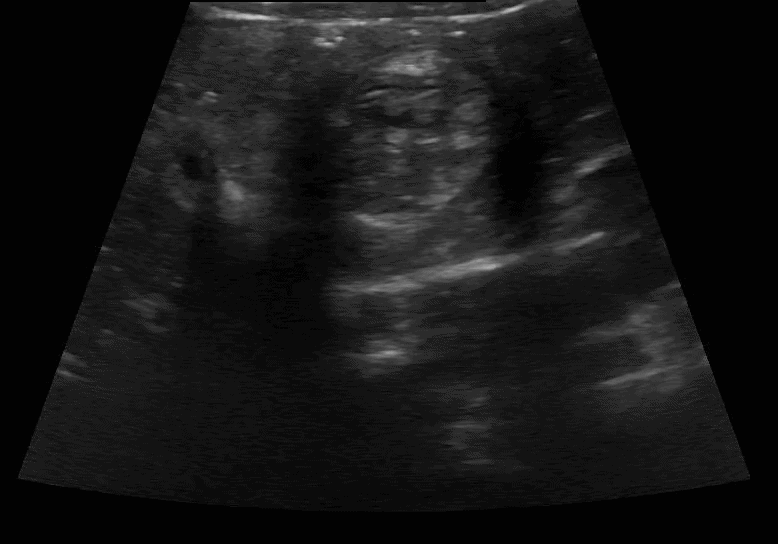

Scanning technique: When evaluating for intussusception with point-of-care ultrasound (POCUS), the infant is placed supine and a high-frequency linear transducer is used initially, with a curvilinear probe available for deeper or larger fields of view. The abdomen is scanned systematically in transverse and longitudinal planes, starting in the right lower quadrant and sweeping through the right upper quadrant, epigastrium, and left abdomen, with particular attention to the periumbilical region and right upper quadrant, where intussusception is most commonly identified. Graded compression is applied to displace bowel gas and improve visualization. On POCUS, intussusception classically appears as a “target” or “donut” sign in the transverse view, characterized by concentric hypoechoic and hyperechoic rings, and as a “pseudokidney” or “sandwich” sign in the longitudinal view. Associated findings may include proximal bowel dilation, free fluid, or absent peristalsis within the involved segment.

Clip 2: Intussusception long axis.